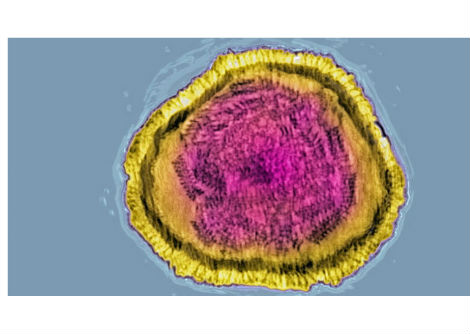

وفي عام 2025 أضافت لجنة نوبل فصلًا جديدًا إلى هذا التاريخ المجيد، إذ منحت جائزة نوبل في الطب لثلاثة علماءٍ أسهموا في كشف أسرار "التسامح المناعي المحيطي" — تلك الآلية الدقيقة التي تحفظ توازن جهاز المناعة بين الدفاع عن الجسم ومنع مهاجمة أنسجته الذاتية. كان هذا الاكتشاف ثمرة عقودٍ من البحث والتجريب، ومثّل تحوّلًا جذريًّا في فهم الطب الحديث لأصل الأمراض المناعية الذاتية. وقد جاء هذا الإنجاز تتويجًا لأعمال فريد رامزدل وشيمون ساكاجوتشي وماري برونكاو الذين كُرِّموا على إسهامهم في حل أحد أكثر ألغاز جهاز المناعة تعقيدًا، وهو كيف يستطيع هذا النظام المعقّد أن يدافع عن الجسم ضد الفيروسات والبكتيريا والخلايا السرطانية من غير أن ينقلب على نفسه ويدمّر خلاياه السليمة.